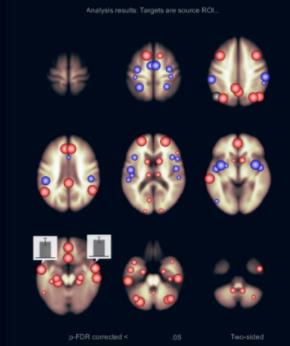

Получены данные о наличии изменений с сети пассивного режима головного мозга при помощи использовании методики функциональной МРТ в покое. Наиболее выраженные изменения отмечаются в функциональной коннективности медиальной префронтальной коры (МПФК), которая играет важную роль в передаче соматосенсорной информации структурам, которые отвечают за моторные и висцеральные реакции, участвуют во внутренней системе вознаграждения и отвечают за принятие решений. Отмечается снижение функциональной коннективности между МПФК и правой дорсальной сетью внимания, правой супрамаргинальной извилиной, а также наблюдалось усиление функциональной связи с задней поясной извилиной, парацингулярной извилиной с обеих сторон, правой латеральной теменной корой, субкаллозальной корой, задней поясной корой, корой предклинья и правой супрамаргинальной извилиной. Отмечается латерализация изменений функциональной связности (преимущественно справа).

|

|

| а) | б) |

| Графическое представление результатов межгруппового статистического анализа, основанного на выборе зоны интереса (ROI-to-ROI): а – карты со схематическим представлением, совмещенные с анатомическим атласом головного мозга; б – 3D реконструкция карты положительных и отрицательных функциональных связей, совмещенных с анатомическим атласом головного мозга |

Пример карты SBC с медиальной префронтальной корой (МПФК) в качестве исходной зоны интереса, фМРТп (статистическая карта, T-тест)